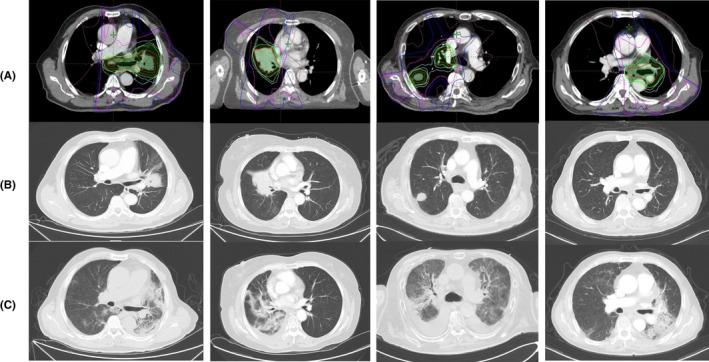

The safety of thoracic radiotherapy (TRT) after programmed death 1/programmed death ligand 1 (PD-(L)1) inhibitor treatment in patients with lung cancer was scarcely reported. This retrospective study was conducted to evaluate the incidence, severity, and risk factors of symptomatic treatment-related pneumonitis in patients with lung cancer who received this sequential combination.

Among the 828 patients with prior PD-(L)1 inhibitor treatment, 96 patients receiving subsequent TRT were included in the analysis. Of these, 49 patients (51%) received radical TRT while 47 patients (49%) received palliative TRT. The median total dose was 52 Gy (IQR 50-60 Gy). The median time from the initiation of PD-(L)1 inhibitor treatment to TRT was 4.8 months (1.6-14.1 months) with most of the patients (74%) administering no less than four cycles of PD-(L)1 inhibitor. During follow-up, 47 patients (48.96%) developed symptomatic treatment-related pneumonitis (grade 2 n = 28, grade ≥3 n = 19) while six patients (6.25%) suffered from fatal toxicity. The median time of pneumonitis onset after completion of TRT was 35 days (0-177 days) with six patients developing during TRT. Pulmonary emphysema and lung V20 were demonstrated to be independent risk factors of symptomatic pneumonitis (OR: 5.67, 95% CI: 1.66-19.37, p = 0.006; OR: 3.49, 95% CI: 1.41-8.66, p = 0.007, respectively).